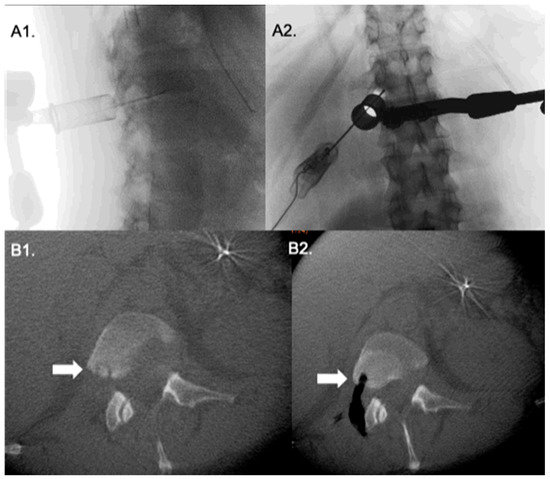

Surgical Technique